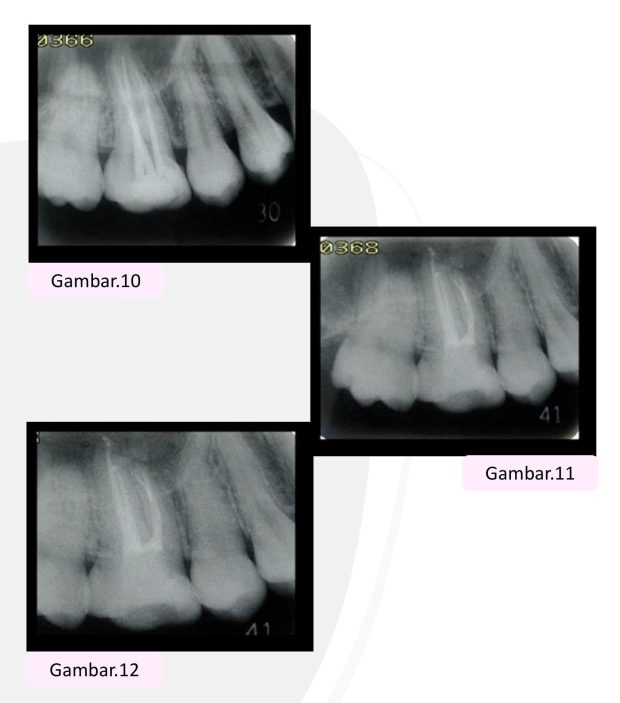

• Master cone ditentukan dan saluran akar dikeringkan dengan paper point (Gambar 10).

• Setelah obturasi, semen glass ionomer digunakan untuk menutup bagian koronal (Gambar 11).

• Pasien diminta datang satu tahun kemudian. Didapatkanprognosis yang baik tanpa gejala klinis dan pemeriksaan penyembuhan periradikuler radiografi menunjukkan seluruhnya (Gambar 12).